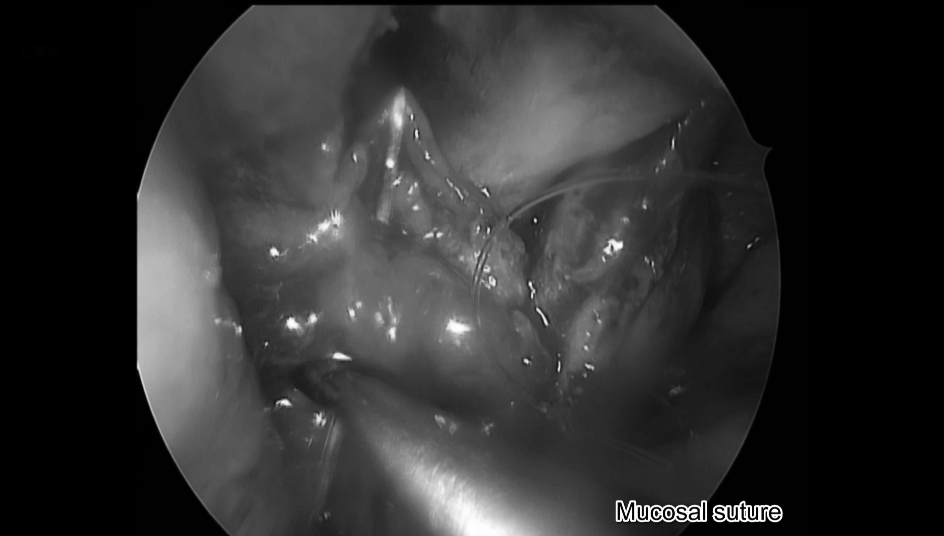

鼻腔内粘膜缝合

▼完成鼻腔内缝合,手术顺利结束

▼鼻腔内缝合示意图